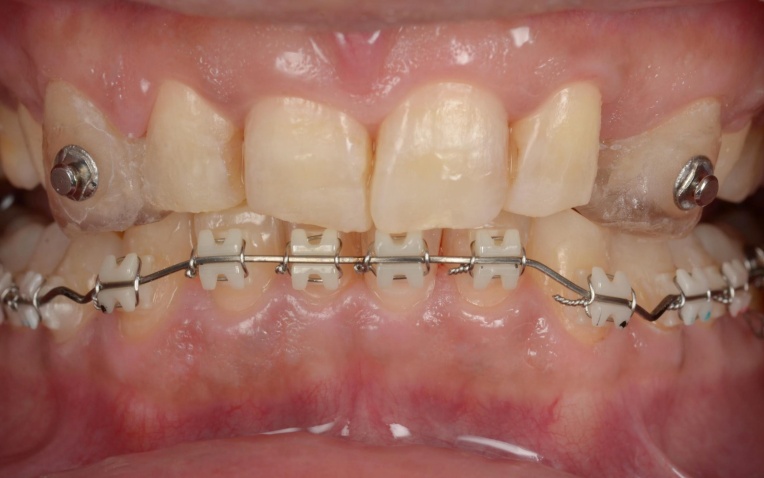

まずはバイト挙上を行います。上顎には、下顎の位置を安定させるための「スプリント」を使用し、下顎奥歯には噛み合わせを調整するための仮歯を装着しました。

この状態で下顎にのみワイヤーを装着し、安定した下顎の位置をキープしながらワイヤー矯正治療へ移行します。

そのため、上顎前歯には上顎のスプリントを必要な部分だけカットして歯に直接接着し、噛み合わせの高さを維持するストッパーとして活用しました。

これにより、上顎の装置が矯正のガイド役となり、安定した下顎の位置を崩さずに精密なワイヤー矯正を行うことが可能です。

また、上顎には上下の噛み合わせの前後関係を整えるための補助装置「顎間ゴム」を使用し、噛み合わせを正しい位置関係へ導く「咬合(こうごう)誘導」を行っています。